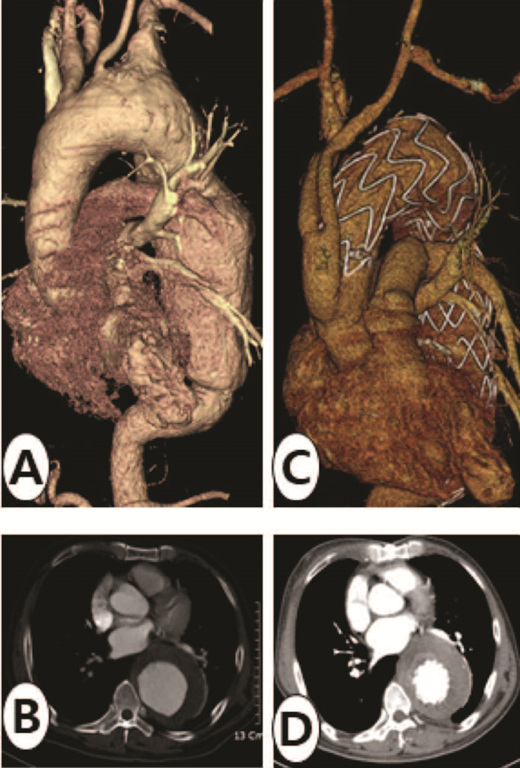

132 하이브리드 수술의 도입